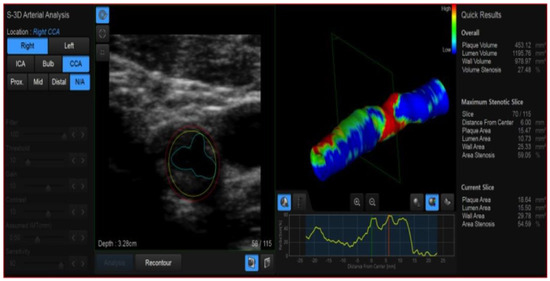

4. Color-Doppler Ultrasound (CDUS)

- Qiu, Y.; Dong, Y.; Mao, F.; Zhang, Q.; Yang, D.; Chen, K.; Shi, S.; Zuo, D.; Tian, X.; Yu, L.; et al. High-Frame Rate Vector Flow Imaging Technique: Initial Application in Evaluating the Hemodynamic Changes of Carotid Stenosis Caused by Atherosclerosis. Front. Cardiovasc. Med. 2021, 8, 617391. [Google Scholar] [CrossRef] [PubMed]

- Murray, C.S.G.; Nahar, T.; Kalashyan, H.; Becher, H.; Nanda, N.C. Ultrasound assessment of carotid arteries: Current concepts, methodologies, diagnostic criteria, and technological advancements. Echocardiography 2018, 35, 2079–2091. [Google Scholar] [CrossRef]

- Grajo, J.R.; Barr, R.G. Duplex Doppler Sonography of the Carotid Artery: Velocity Measurements in an Artery With Contralateral Stenosis. Ultrasound Q. 2007, 23, 199–202. [Google Scholar] [CrossRef] [PubMed]